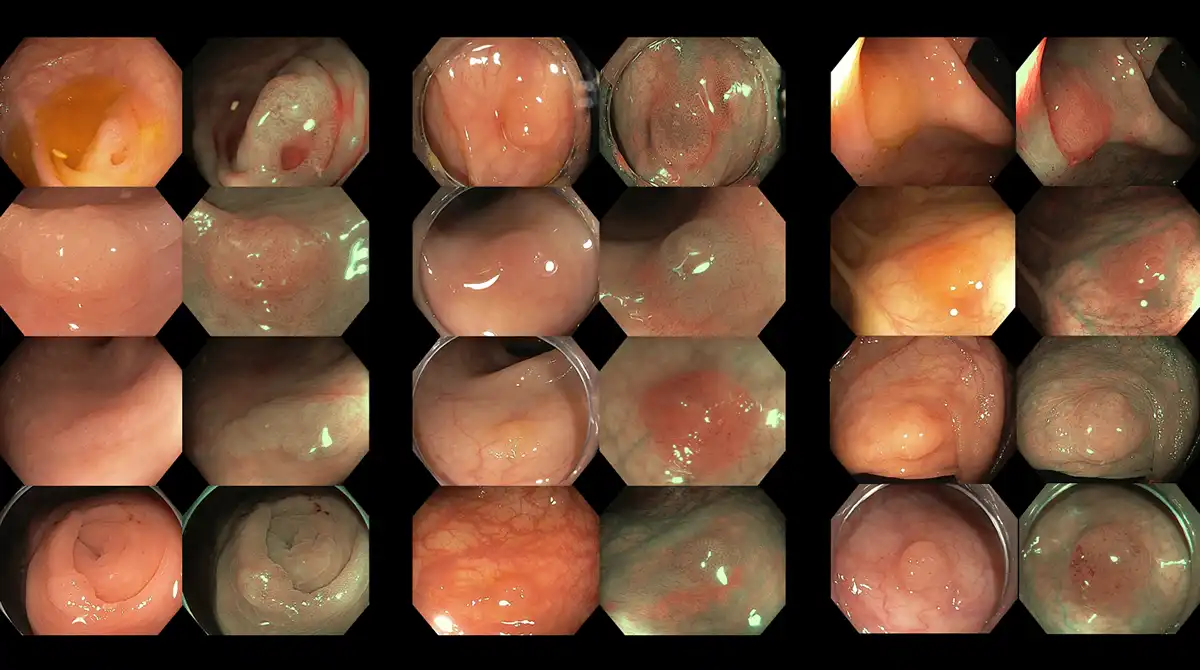

Figure 5: Subtle colorectal polyps detected with high-definition colonoscopy and characterized with image-enhanced endoscopy

Thus, colonoscopy is an essential tool and a gold-standard diagnostic procedure for achieving these objectives. The recommended age to begin screening has been lowered to 45 years, with earlier screening advised for individuals with specific risk factors, such as a positive family history of colorectal cancer, hereditary or genetic conditions, and/or inflammatory bowel disease.